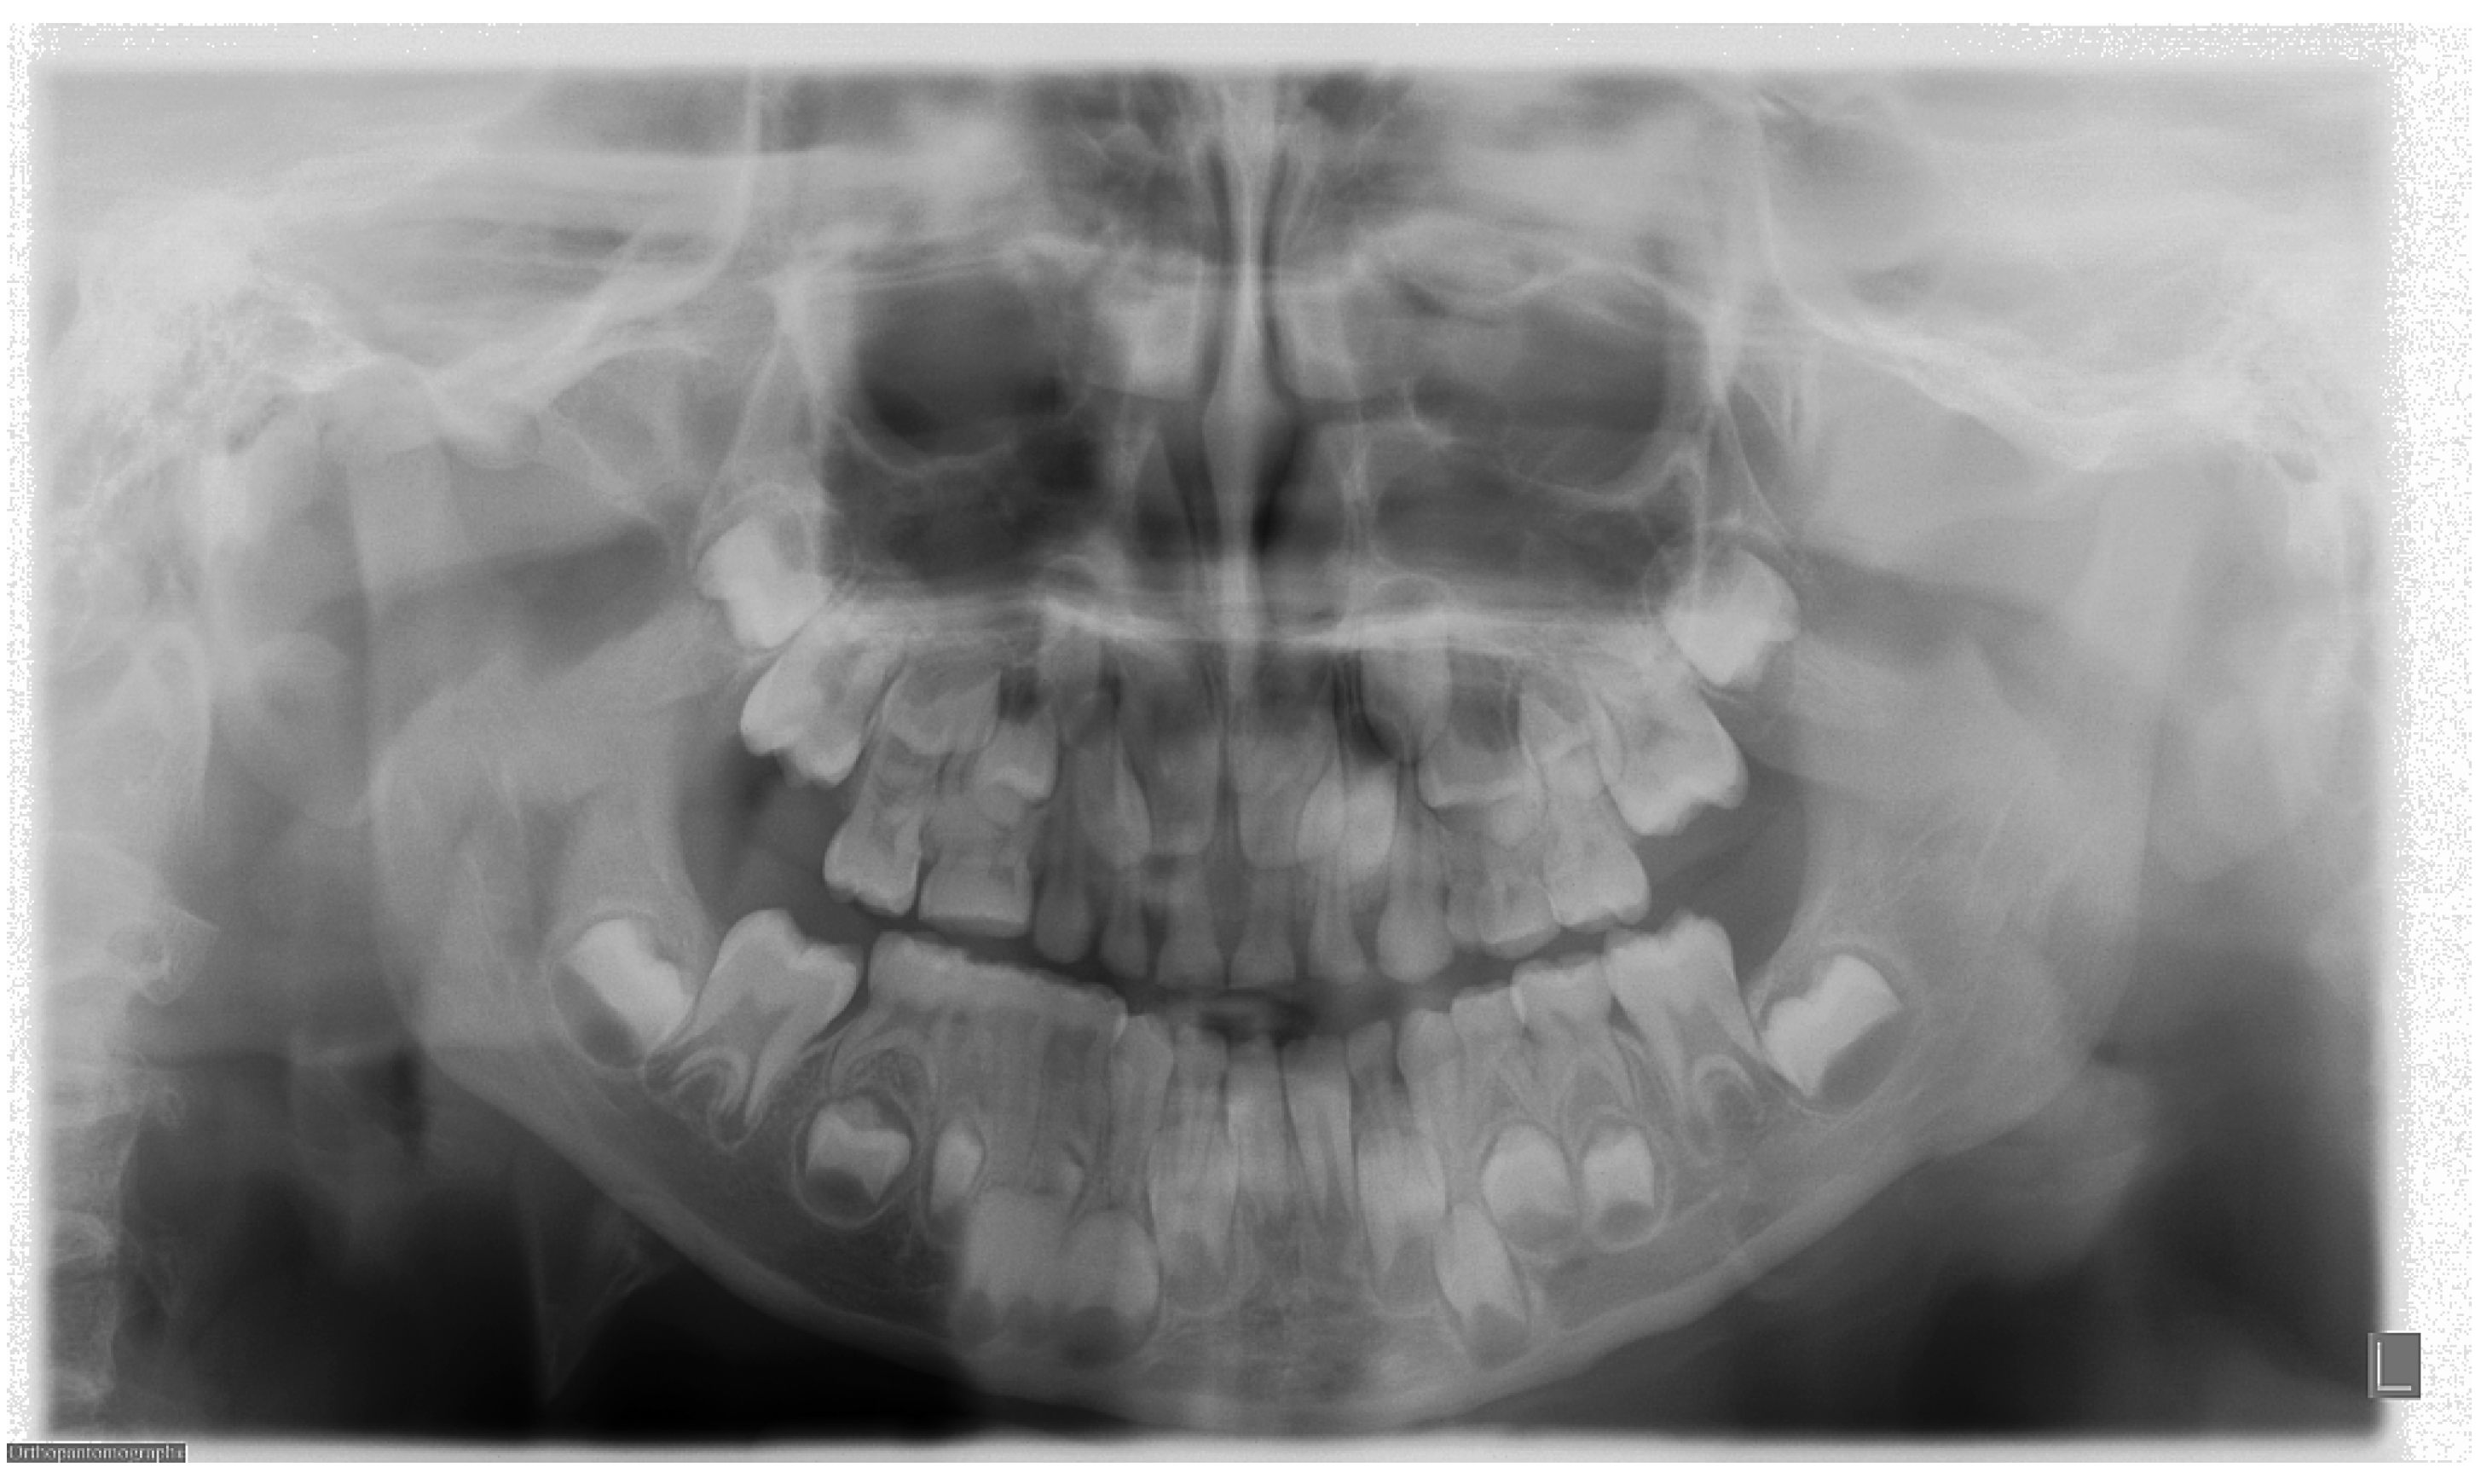

4. Frequency of Errors in PAN Performance and Interpretation

5. The Importance of Head Orientation

6. Evaluation of PAN Examination